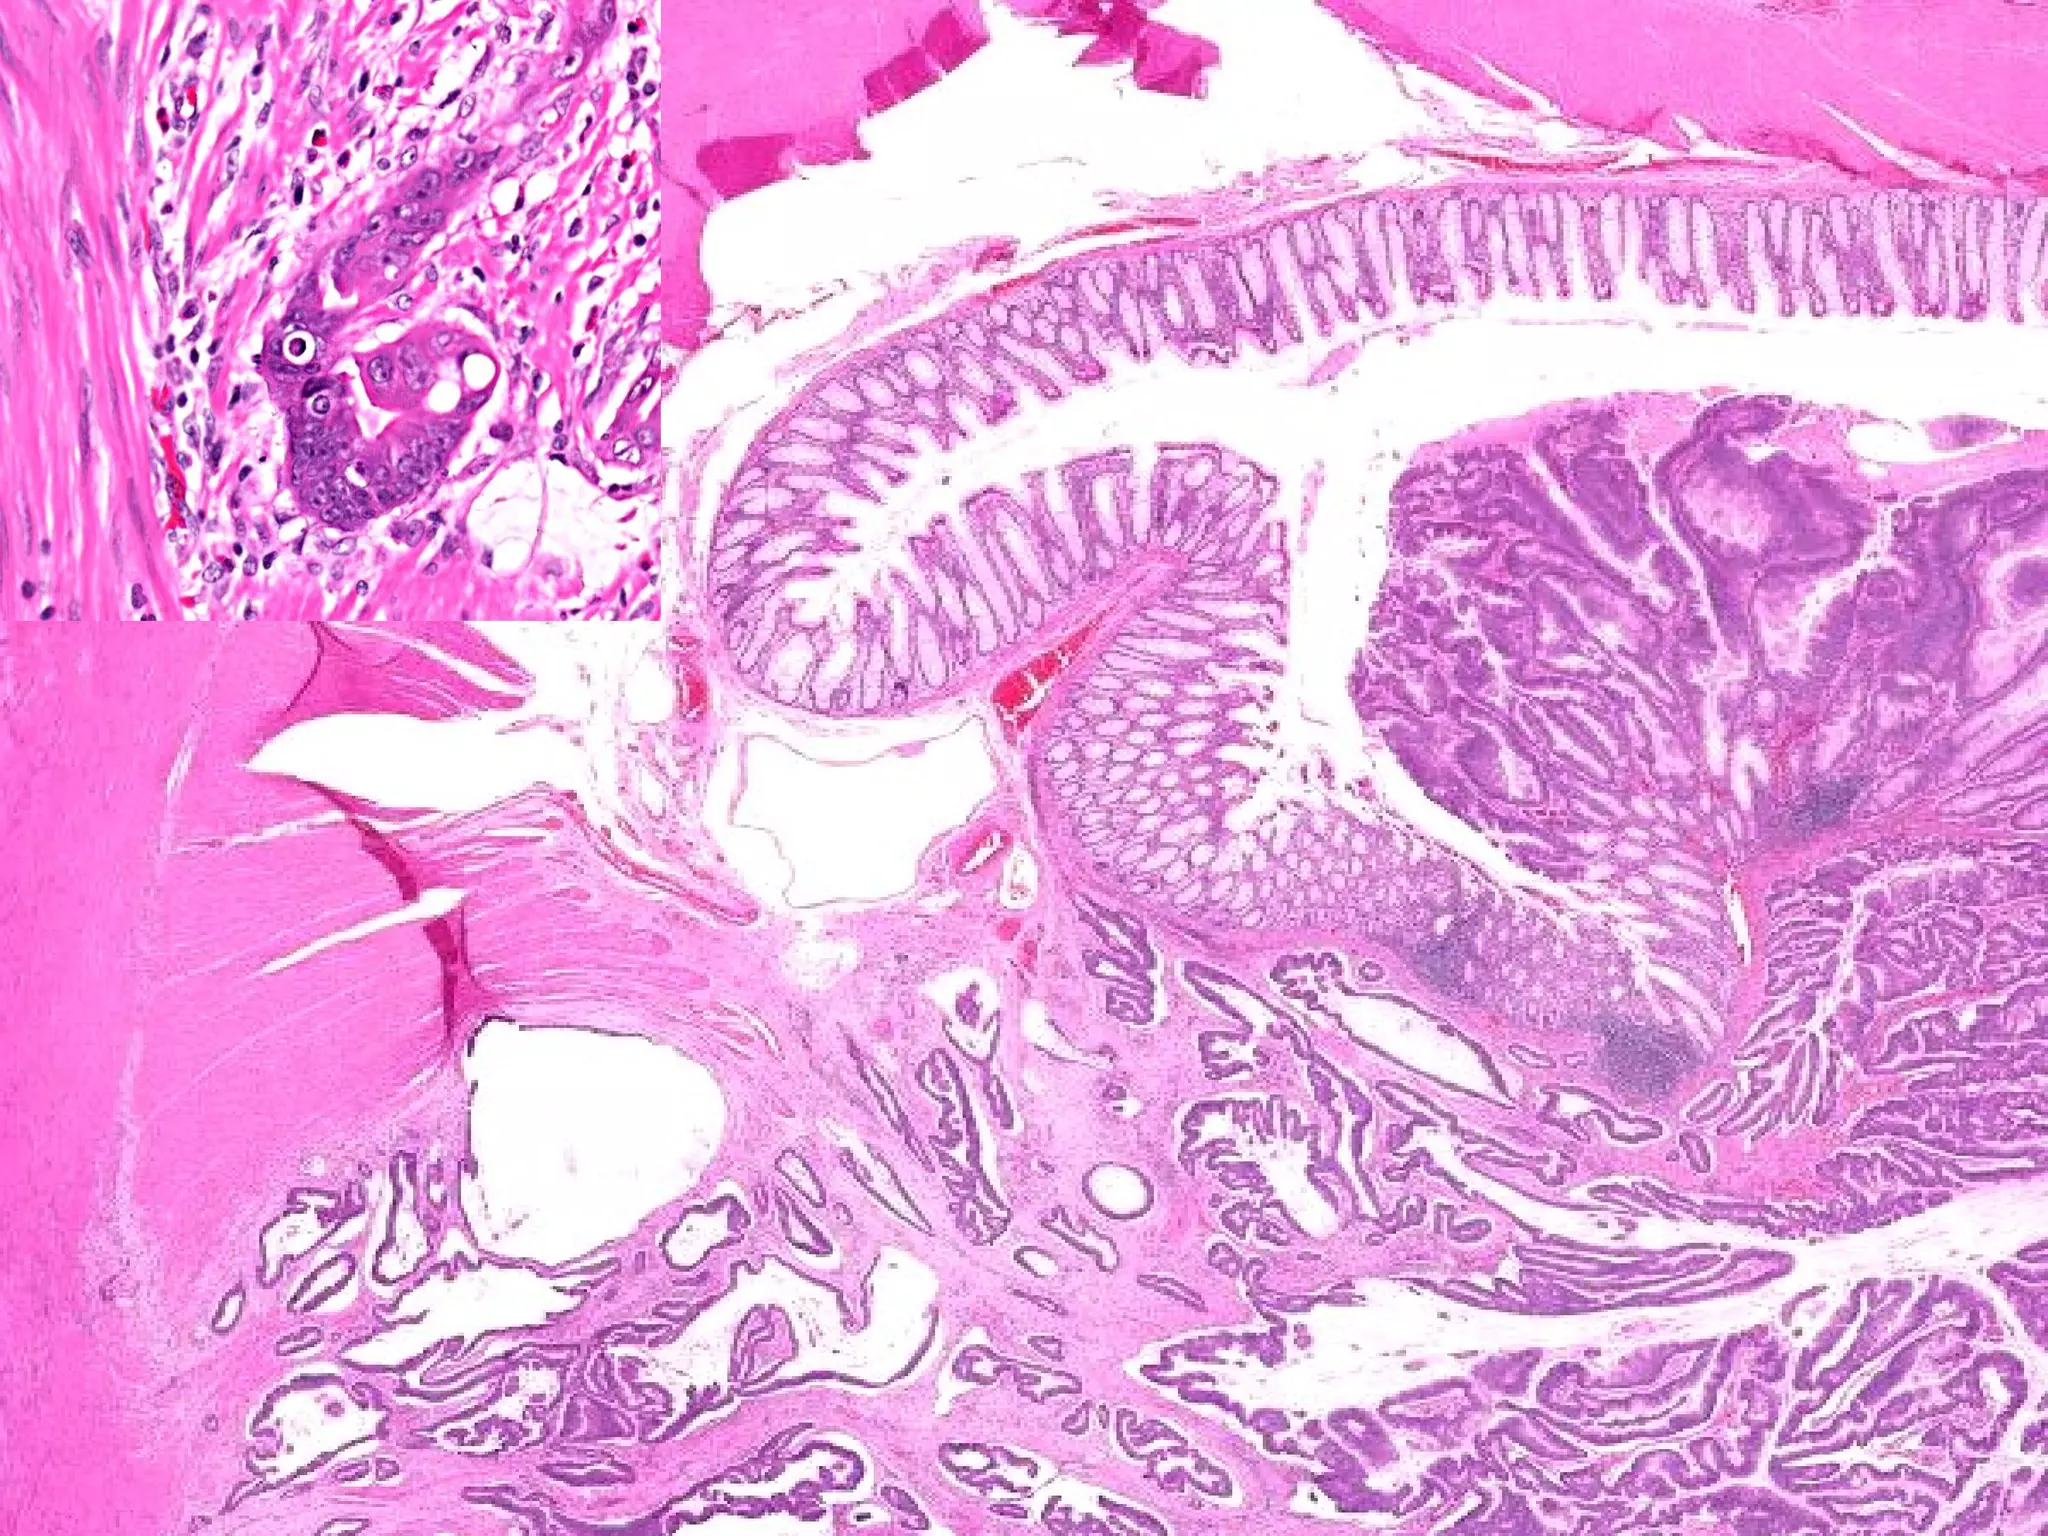

BARRETT’S ESOPHAGUS Can be defined as intestinal metaplasia of a normally SQUAMOUS esophageal mucosa.  The presence of GOBLET CELLS in the esophageal mucosa is DIAGNOSTIC. SINGLE most common RISK FACTOR for esophageal adenocarcinoma 10% of GERD patients get it “ BREACHED” G-E junction

BARRETT’S ESOPHAGUS INTESTINALIZED (GASTRICIZED) mucosa is AT RISK for glandular dysplasia. Searching for dysplasia when BARRETT’s is present is of utmost importance MOST/ALL adenocarcinomas arising in the esophagus arise from previously existing BARRETT’s

• #28 Barrett’s on top, goblet cell on right, normal esophagus on bottom.

• #30 Glandular “dysplasia”